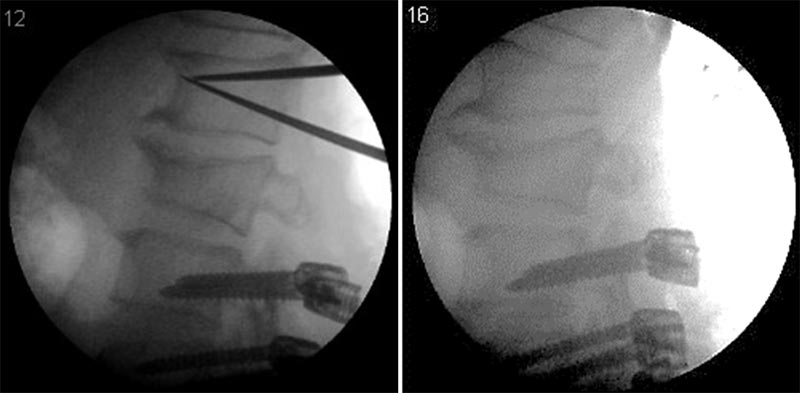

Osteotomia de Subtração pedicular. (Acervo dos autores)